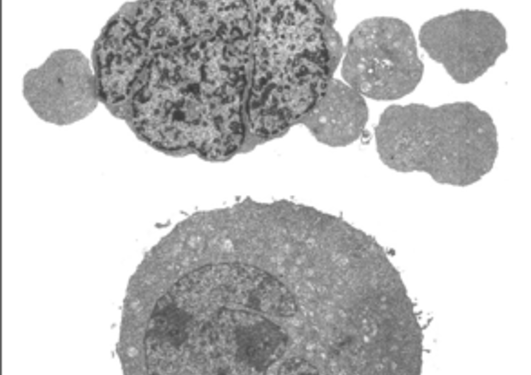

The mechanisms of cancer cell drug resistance is still not fully understood.